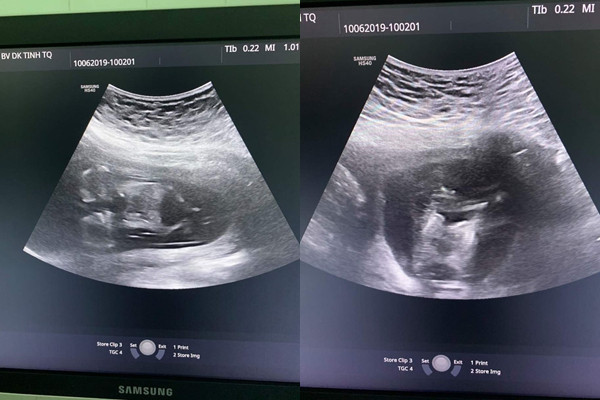

| Hình ảnh siêu âm cho thấy 2 thai nhi dính nhau từ ngực tới bụng, chung 1 quả tim hết sức hiếm gặp |

Chị P. mang thai lần đầu, có thai tự nhiên. Kết quả khám thai của chị P. cho thấy đang mang song thai ở tuần thứ 12. Điều đặc biệt là 2 thai dính nhau từ phần phần ngực xuống đến phần bụng, có chung một quả tim và cả 2 thai đều có tăng khoảng sáng sau gáy (2,5mm và 8,0mm), dấu hiệu sớm của hội chứng down.